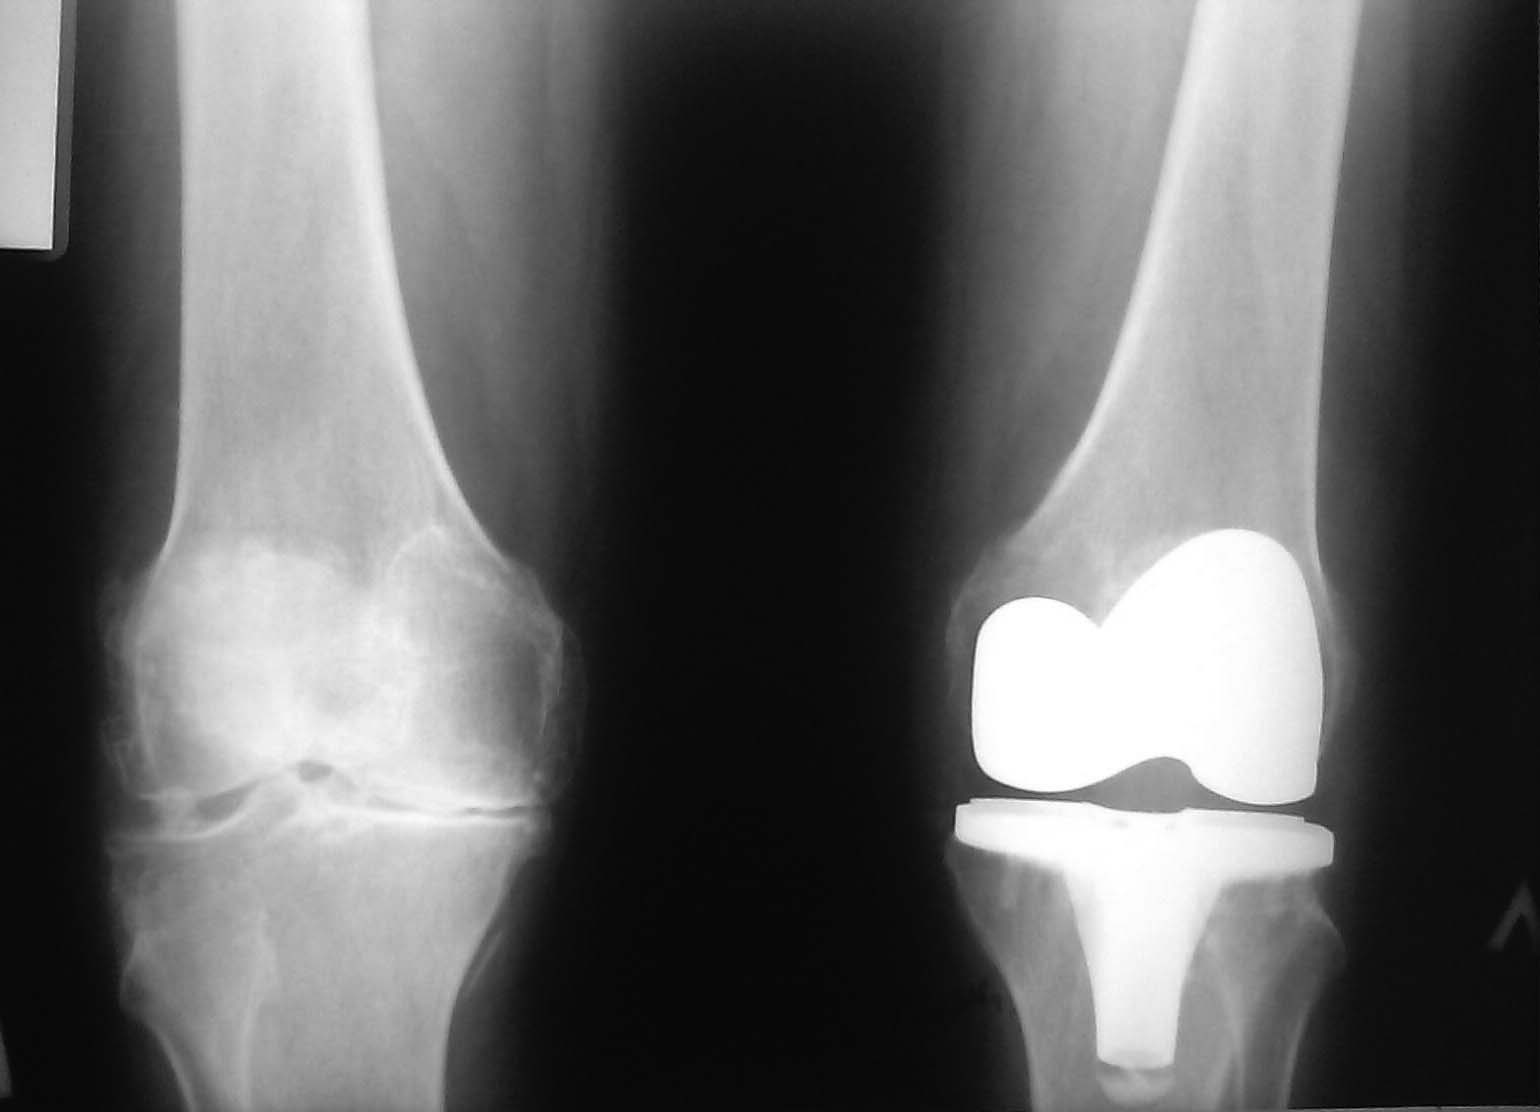

Re: хронический синовит после ТЭП

вот еще боковая проекция.

Спасибо коллеги за помощь.Представляю Вашему вниманию аксиальную проекцию (почему то второй сустав не сделали и качество только такое).